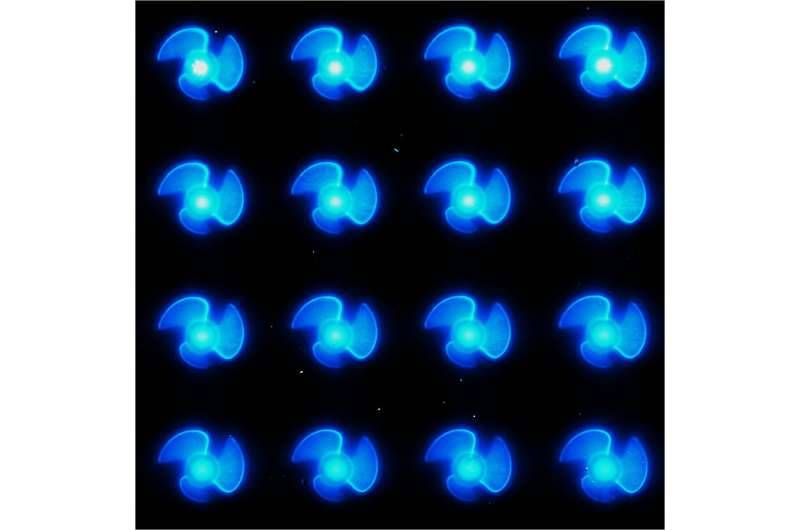

صمم المهندسون من جامعة كولورادو الأمريكية فئة جديدة من «الروبوتات الدقيقة» تبلغ عرضها 20 ميكرومتراً قادرة على علاج الأمراض التي تصيب الإنسان مثل التهاب المثانة الخلالي، وهو مرض مؤلم يصيب المثانة ويصيب ملايين حول العالم، إضافة إلى تطويرها للعديد من الأمراض البشرية.

ويشير مصطلح الروبوتات الدقيقة إلى مجال الروبوتات المصغرة، وبالأخص الروبوتات المتحركة ذات الأبعاد المميزة الأقل من 1 مم ذاتية الدفع يمكنها المرور عبر السائل بسرعات كبيرة ووفقاً للمطورين ستوصل الأدوية الموصوفة إلى أماكن يصعب الوصول إليها داخل جسم الإنسان.

وأضاف: «يبلغ عرض كل روبوت 20 ميكرومتراً فقط، وهي أصغر بعدة مرات من عرض شعرة الإنسان وهي سريعة جداً، وقادرة على السفر بسرعات تبلغ حوالي 3 ملم في الثانية، أو ما يقرب من 9000 ضعف طولها في الدقيقة».

يصنع الفريق الروبوتات الدقيقة الخاصة به من مواد تسمى «البوليمرات المتوافقة حيوياً» باستخدام تقنية مشابهة للطباعة «ثلاثية الأبعاد».

وتأتي الروبوتات بـ3 زعانف صغيرة، كما أنها تتضمن شيئاً إضافياً مختلفاً عن كل الروبوتات فهو يحمل فقاعة صغيرة من الهواء المحبوس، إذا قمت بتعريض الروبوتات إلى مجال صوتي، مثل النوع المستخدم في الموجات فوق الصوتية، فستبدأ الفقاعات في الاهتزاز بشدة، ما يدفع الماء بعيداً ويطلق الروبوتات للأمام وهي جزء من طريقة عملها.